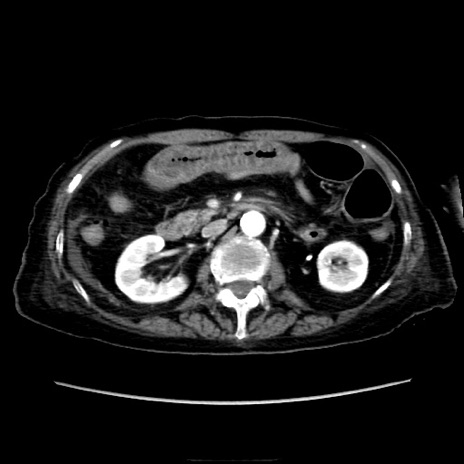

症例40(横断像)

【症例】90歳代女性

【主訴】腹痛・嘔吐

【現病歴】 食欲低下、嘔吐があり昨日他院受診。肺炎と診断され入院となる。入院後より腹部全体に圧痛あり。胃管留置され経過みていたが、症状持続するため、

当院転院となる。

【既往歴】胸椎圧迫骨折、胆石症

【身体所見】腹部:中央に激痛あり、圧痛あり、反跳痛不明

【データ】WBC 17100、CRP 18.82

横断像